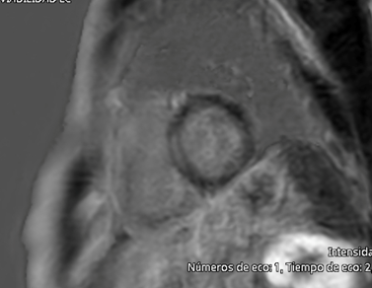

An echocardiogram showed normal left ventricular size (end-diastolic diameter 52 mm), normal left ventricular ejection fraction (58%), maximal wall thickness of 11 mm, a non-dilated right ventricle with preserved systolic function (TAPSE 21 mm), and a mildly dilated left atrium (indexed left atrial volume of 30 mL/m²). Laboratory tests, including complete blood count, creatinine (0.9 mg/dL), potassium (4.2 mmol/L), creatine kinase (85 U/L), and NT-proBNP (110 pg/mL), were all within normal ranges. A cardiac MRI was performed, showing mid-myocardial late gadolinium enhancement in the basal-to-mid septal region, with normal left and right ventricular dimensions and systolic function. However, the left atrium was moderately dilated (indexed left atrial volume 42 mL/m²) (Figure 3).